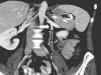

Radiología Síndrome del cascanueces

Síndrome del cascanueces

Nutcracker syndrome